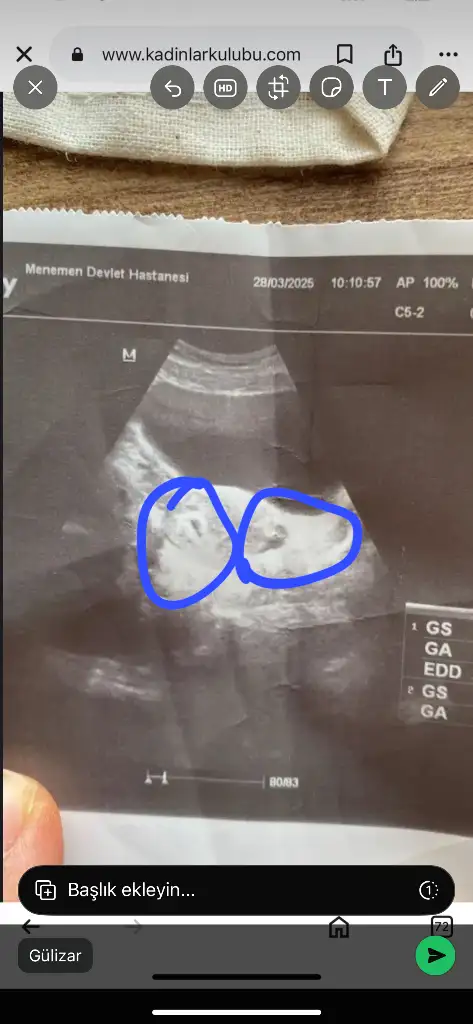

Nasıl gördün iki kese neredeEvet iki kese gördüm

Bak biri daha küçük diğeri biraz daha büyük ama zamanla kapanır o farkVallahi bende anlamadım canım

Ay valla ne bilim ben anlayamadım senin dediğin gibi gözüküyorda neden böyle çekmiş doktor neden yakınlaştırmamış acaba devlet farkı gerçekten yaBak biri daha küçük diğeri biraz daha büyük ama zamanla kapanır o fark

Bak iki kese ikizlerDevlet hastanelerinin cihazları biraz daha eski sanırım özellere göre o sebepten kalite ve görüntü pek net olmuyor ola bilir mi acaba

Ultrason eski olabilir onun için ama belli iki kese varAy valla ne bilim ben anlayamadım senin dediğin gibi gözüküyorda neden böyle çekmiş doktor neden yakınlaştırmamış acaba devlet farkı gerçekten ya

Allah razı olsun canım daha güzeli senin olsun Allahın izniyle sen bana müjdemi verdin rabbimde sana müjdeni versin inşallahBak iki kese ikizleryolda ama diğeri daha küçük inşallah zamanla kapanır o fark yeter ki sağlıcakla büyüsünler